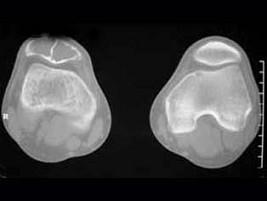

问题 患者,男性,30岁,近2年来感右膝疼痛,活动后加重,2周前由于剧烈运动后,右膝活动受限,右膝压痛明显,有波动感,皮肤稍显红肿,以髌骨部明显,请结合所提供图像,选择最佳选项 ( )

选项 A、骨巨细胞瘤 B、动脉瘤样骨囊肿 C、非骨化性纤维瘤 D、骨囊肿 E、纤维性骨皮质缺损

答案 B